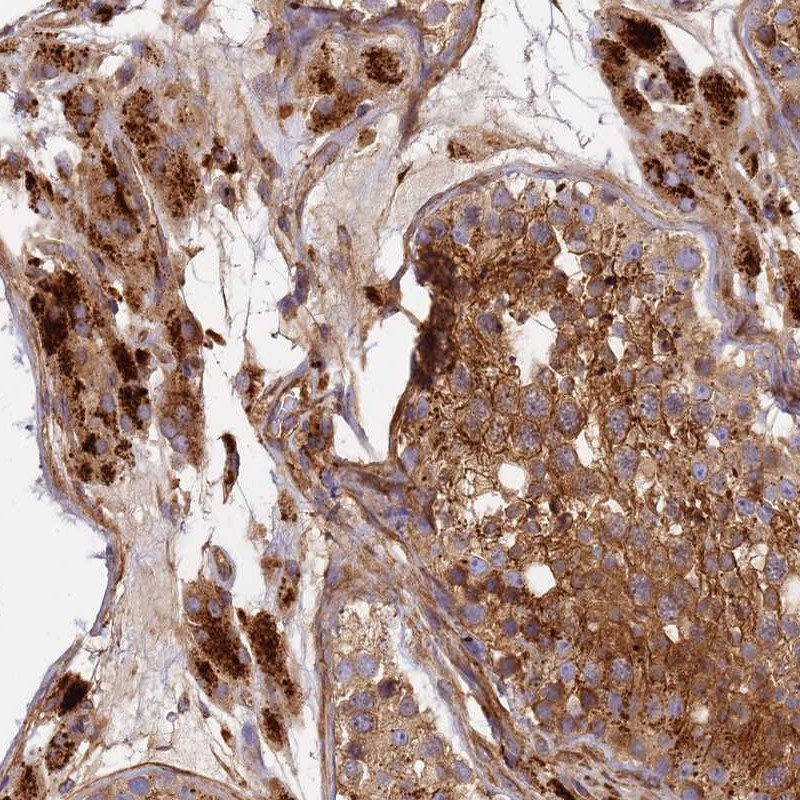

Immunohistochemical staining of human testis shows strong cytoplasmic positivity in cells in seminiferus ducts and Leydig cells.